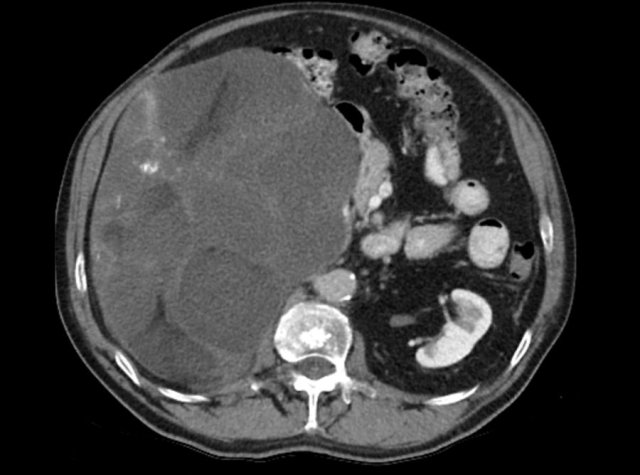

This axial venous CT shows a very bulky right adrenal mass, suspicious for a malignancy, based on the large size and heterogeneity.

This lesion is an adrenocortical carcinoma, but in contrast to the former example, subsequent FDG PET-CT performed for staging purposes showed only mild uptake and only in the most avidly enhancing part of the tumor.

Most adrenocortical carcinomas show intense FDG-uptake.

This lack of FDG-avidity might be due to a lower grade tumor with lower mitotic rate or large hemorrhagic or necrotic components.